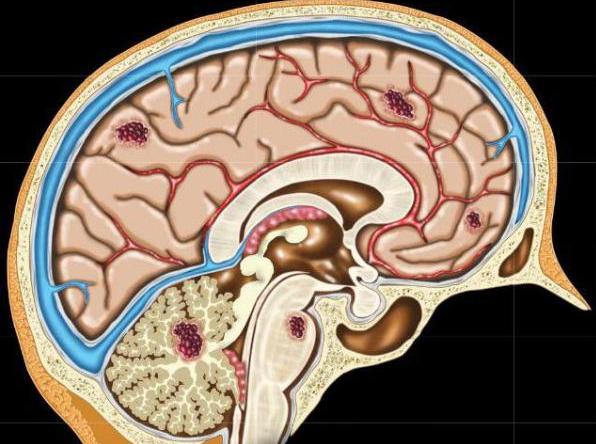

Кавернома или кавернозная ангиома головного мозга является опухолью, которая не связана с общим кровотоком. Обнаружить ее можно в любой области головного мозга: чаще всего – в коре больших полушарий, также в таламусе, мозолистом теле, стволе мозга, желудочках мозга.

Кавернома (код по Мкб 10 – D33) представляет собой мозговое новообразование в виде сосудистых полостей (каверн), в которых находятся воздух или продукты распада крови. Эти продукты распада состоят из тромбов, соединительной ткани и т.д. Величина каверном и число их может быть различным – несколько новообразований могут прилегать вплотную одна к другой или находиться на некотором отдалении друг от друга. Кавернозная ангиома имеет шишковатую поверхность синюшного цвета разнородной структуры, у опухоли есть четкие границы, отграничивающие ее от остальных тканей, чаще всего она округлой формы. Перегородки между полостями состоят из волокнистой плотной ткани. Размеры каверномы могут быть различны – от совсем маленьких до нескольких сантиметров в диаметре.

Множественные кавернообразования встречаются в 10-15 % случаев. Такие каверномы имеют предрасположенность к частым кровоизлияниям, и мозговое вещество, которое их окружает, вследствие этого становится желтоватого цвета.